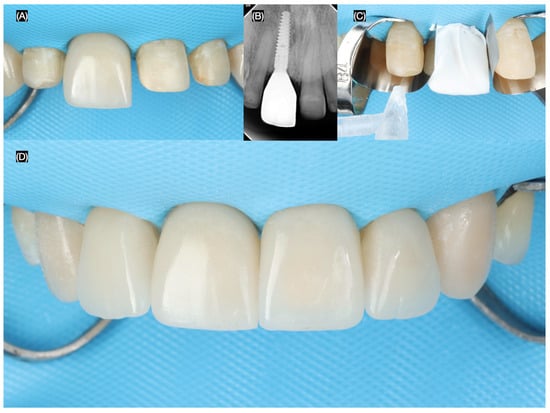

The final screw-retained implant crown was placed, ensuring proper fit, occlusion, and esthetics. A dental dam was then applied to achieve total isolation for the cementation of the veneers, ensuring a clean and controlled environment. The tooth surfaces were first prepared using sandblasting, followed by etching with phosphoric acid. The lithium disilicate veneers were treated with hydrofluoric (Porcelain Etchant, Bisco, Schaumberg, IL, USA) acid for 20 s, thoroughly cleaned in an ultrasonic water bath for 5 min, and coated with a silane (Porcelain Primer, Bisco, Schaumberg, IL, USA) coupling agent for 60 s. Finally, the veneers were bonded using universal adhesive (All Bond Universal, Bisco, Schaumberg, IL, USA) and dual-cure resin cement (Choice 2 Veneer Cement, Bisco, Schaumberg, IL, USA), ensuring a durable and esthetic outcome (Figure 8 and Figure 9).

Figure 8.

Final tooth reparations and impression. (A) Implant impression, (B) radiograph with impression post, (C) tooth preparation with reduction guide, and (D) frontal view of contoured soft tissue and tooth preparations.

Figure 9.

Placement of the final restorations under dental dam isolation. (A) Implant restoration, (B) radiograph of implant restoration, (C) tooth surface treatment with sandblast, and (D) final cementation of restorations.

The patient expressed complete satisfaction with the final restorations, praising the natural shade and shape of the teeth. To protect the restorations from potential damage, the patient was provided with a custom-made night guard. Detailed oral hygiene instructions were given, emphasizing the importance of maintaining the health of the restorations and surrounding tissues. The patient was scheduled for regular follow-up visits every six months for professional dental prophylaxis and to monitor the condition of the restorations and periodontal tissues (Figure 10). At the three-year follow-up visit, the patient was still satisfied with the outcome.

Figure 10.

Final restorations.